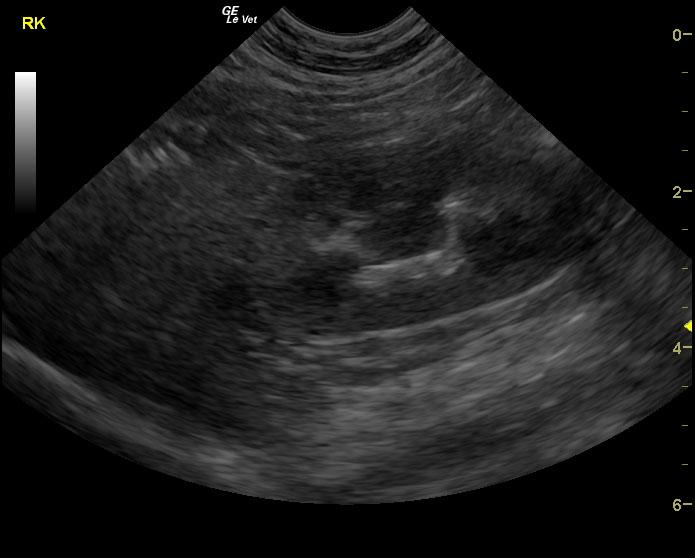

The urinary bladder in this patient revealed dependent debris that measured 2.1 cm in length. The bladder wall presented minor, apical ventral wall thickening. Suspended debris was also evident. The bladder wall thickening appeared to be concentric throughout with some loss of mural detail, and measured 0.4 cm at minor repletion. The pelvic urethra was also thickened. These images are most consistent with interstitial cystitis with minor potential for bladder lymphoma. The kidneys revealed largely normal size and structure; corticomedullary definition and ratio (cortex 1/3 of medulla) were essentially maintained with minor loss of curvilinear pattern. The cortices presented largely uniform texture with some echogenic changes that are not likely of clinical significance at this time.